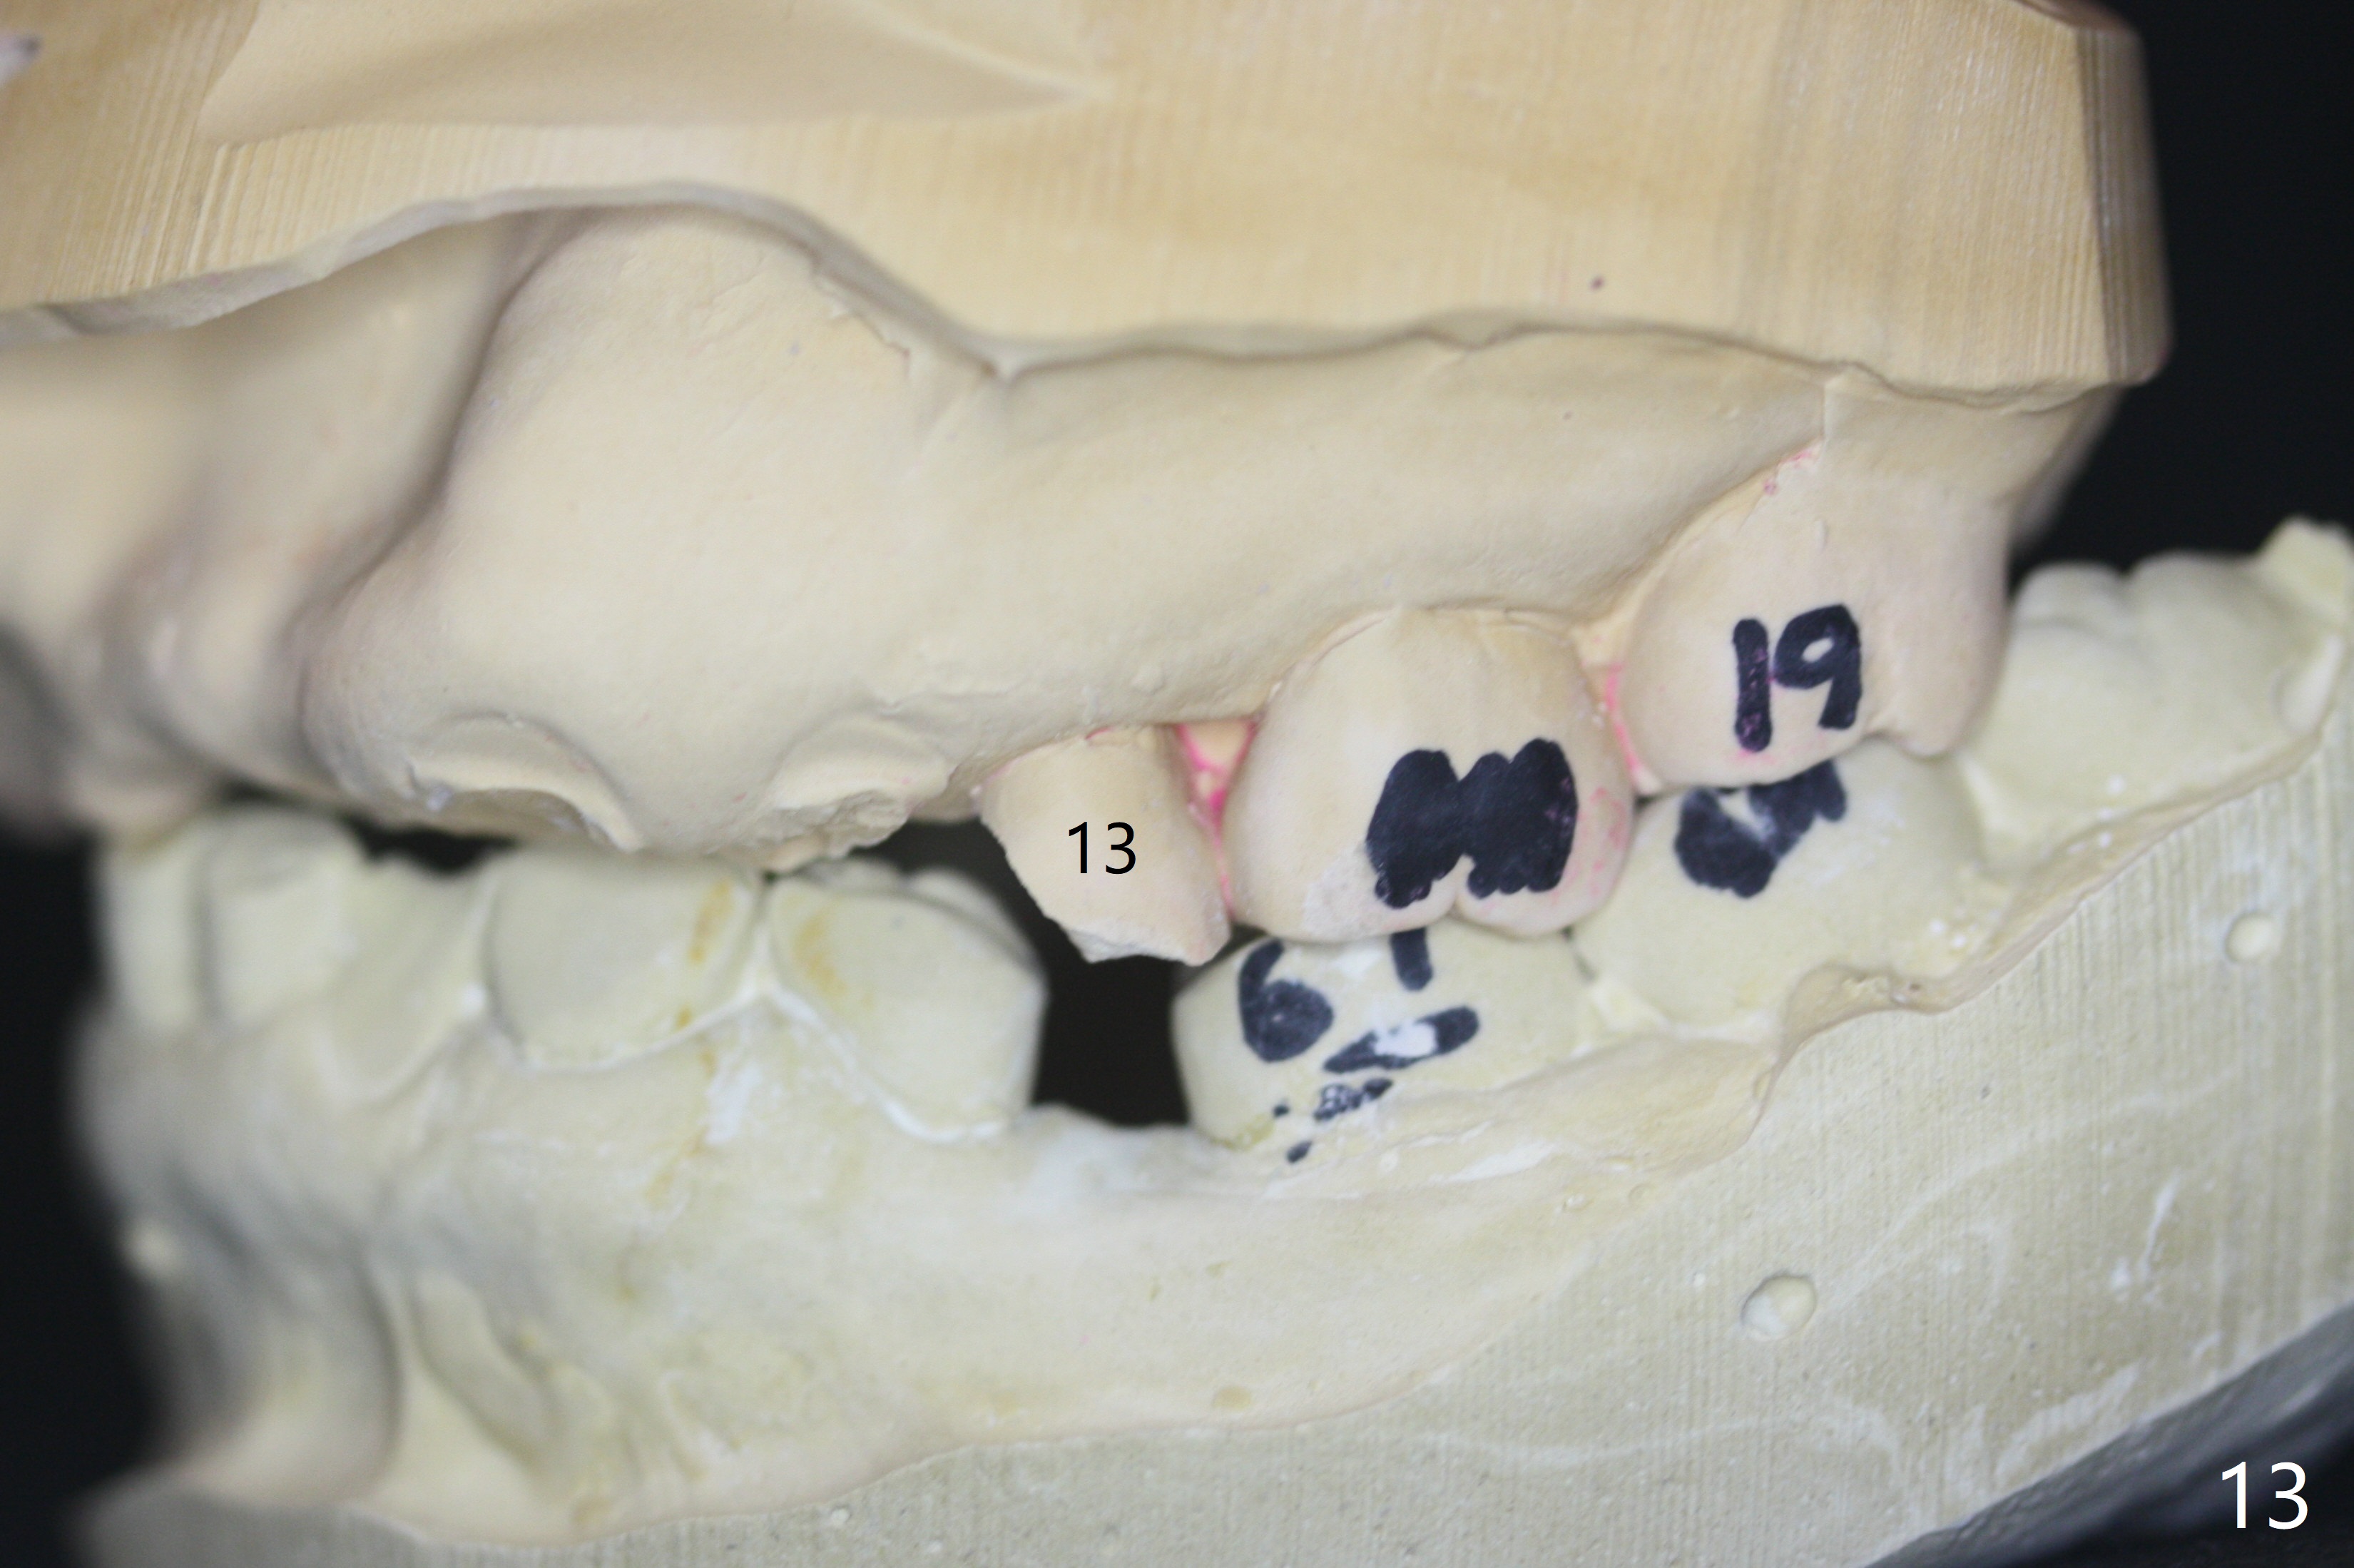

It is smooth and quick to finish osteotomy with guide at #6,7,10-12, but when 3 mm 1-piece implants are placed free hand at #7 and 10 (Fig.1,2), the gingival parts of the abutments contact the incisal edges of the lower incisors (anterior deep bite) in spite of effort to change the trajectory by repeated back and forth placement after use of Lindamann bur buccally. Following an immediate provisional (Fig.3,4), the occlusal surface of the posterior teeth are raised to eliminate anterior restoration interference. Immediate postop CBCT shows that the implants at #7 and 10 could be placed more buccally (Fig.6,7, as compared to the normal position at #6,11,12 (Fig.5,8,9)). Fig.10 was taken 2 days preop, while Fig.11-13 postop. Can we change 1-piece implants (3mm) at #7 and 10 to 2-piece one (3.5) and use angled or cementation abutments for easy restoration (Fig.14-16)?